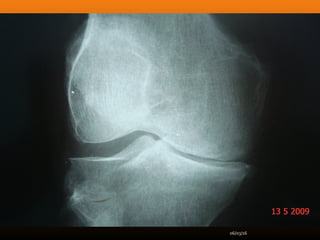

RADIOLOGIA

No início da doença não se observam anormalidades. Com seu

desenvolvimento, observam-se:

 Diminuição do espaço intra-articular

 Esclerose subcondral (eburnação)

 Osteófitos;

 Erosão e anquilose óssea (pseudocistos ósseos).